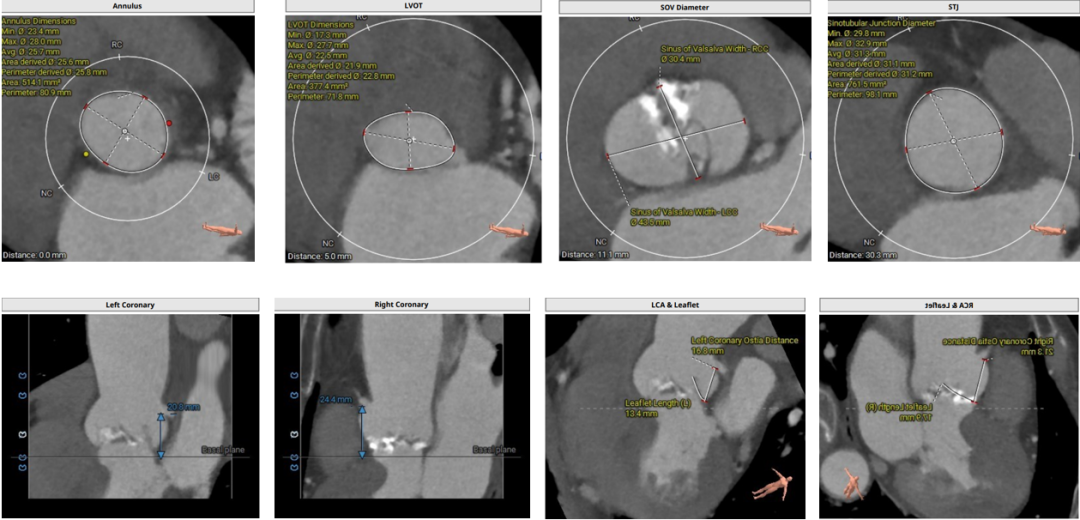

术前评估:

1.主动脉瓣瓣环周长80.9mm,平均周长径25.8mm;

2.Type0型二叶式主动脉瓣,中度钙化,瓣叶增厚,左室流出道呈收口状;

3.左右冠共窦,冠脉开口高度可,左、右冠瓣叶长度<冠脉开口到瓣叶附着缘距离;

4.瓦式窦、窦管交界、升主动脉内径尚可;

5.瓣环水平夹角66°,横位心,主动脉弓宽度、角度可;

6.双侧外周入路行走适宜,未见明显迂曲。

主动脉根部评估:

根部评估

图片

瓣上评估